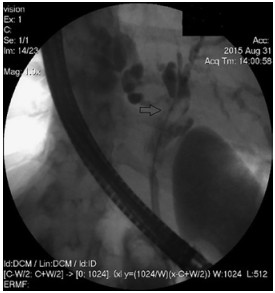

Abstract: Hilar cholangiocellular carcinoma (CCC) is a malignant neoplasm of epithelial origin occurring at the confluence of the right and left hepatic bile ducts. Typically, these tumors are small, poorly differentiated, exhibit aggressive biologic behavior with non-specific symptoms and tend to obstruct the intrahepatic bile ducts. Surgery is the only available curative option. Unfortunately, in less than half of the patients a complete resection is possible with poor survival rate in unresectable cases. In this report, we present the case of a 58-year-old woman with a history of unresectable hilar cholangiocarcinoma. Initially she was treated with intraductal dilatation of malignancy and placement of a plastic stent and chemotherapy (Gemcitabin® and Platinol®). Two years later she underwent a second-line chemotherapy with Gemcitabin® and Oxyplatin® because of tumor progression. Despite a second line chemotherapy and placement of an uncovered self-expandible metal stent (ucSEMS) that was extended later on by stent-in stent technique, there was tumor progression which led to a complex course with relapsing obstructive cholangiosepsis and cholestasis. Because of tumor ingrowth, endobiliary radiofrequency ablation of the malignant stenosis was performed in repeated sessions. This case illustrates that radiofrequency ablation of solitary malignant biliary obstruction is feasible, safe and allows an improvement of quality of life in non-operable patients.